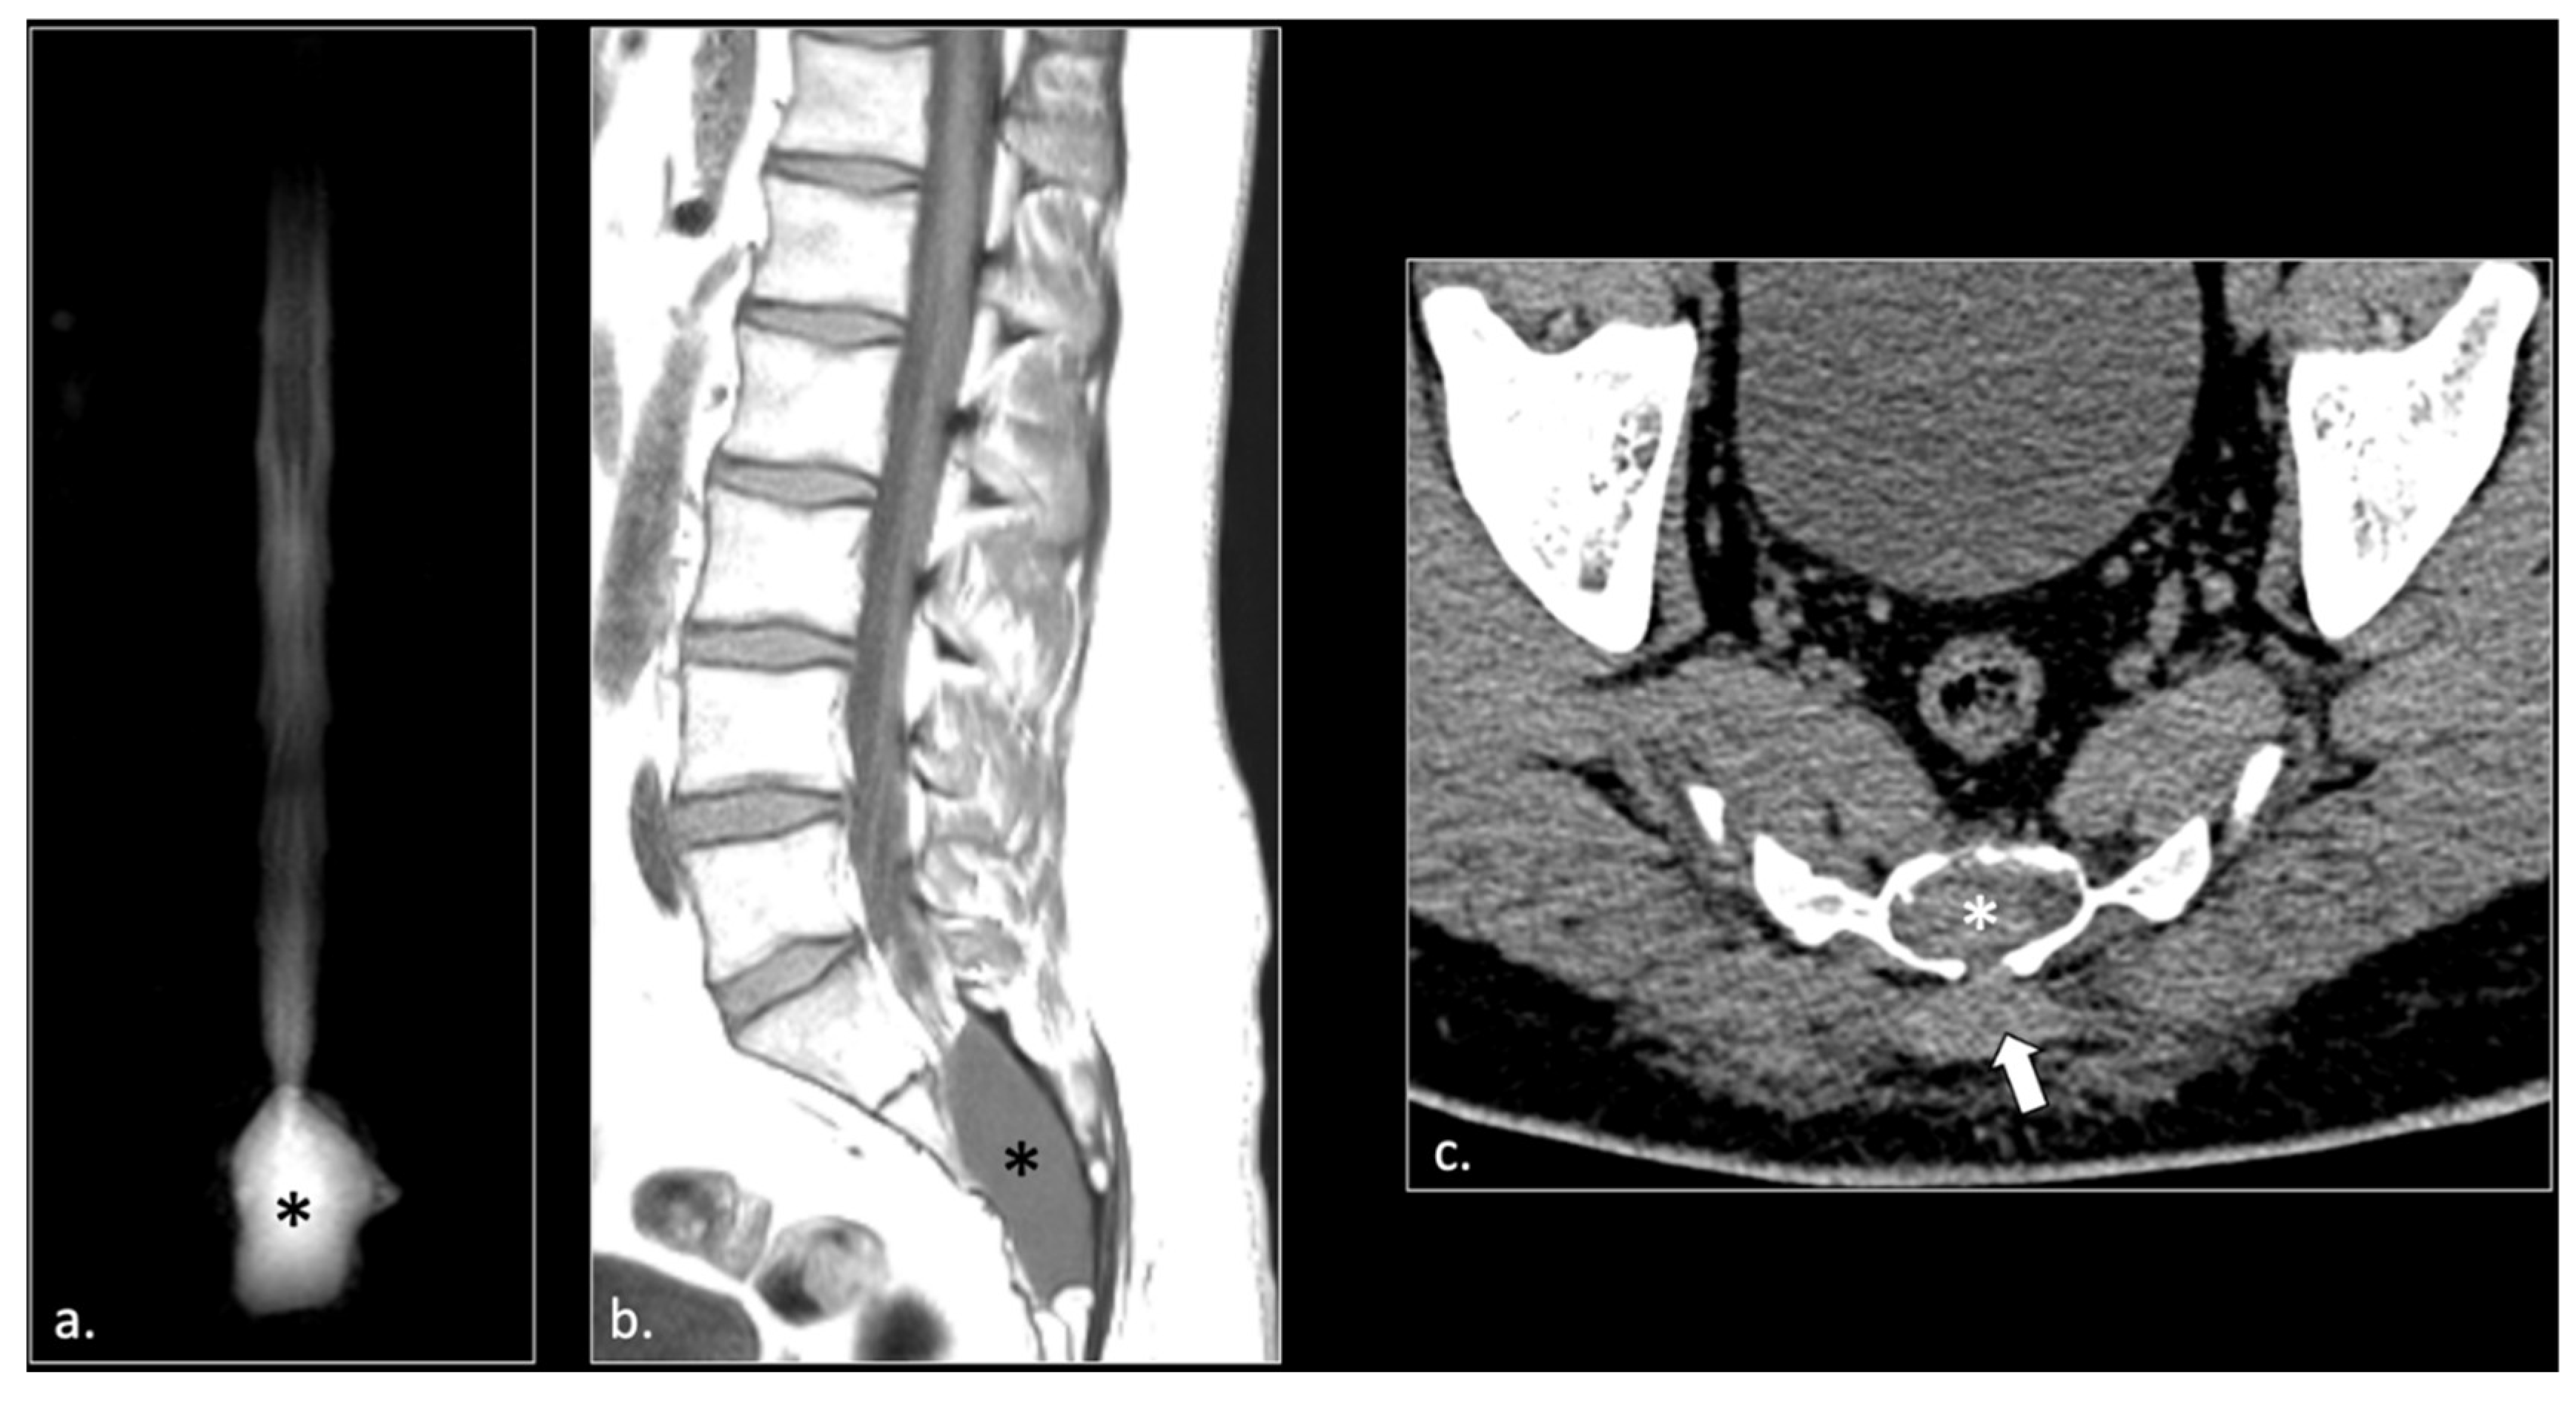

Figure 2.

A 24 years-old male with chronic pudendalgia. The onset of pudendalgia could be referred to a sacral trauma. (a) Coronal MRI myelography shows a large Tarlov cyst into the sacral canal (*). (b) Sagittal T1 scan of the lumbar spine demonstrates slight hyperintensity of the cyst, due to chronic hemorrhage (*). (c) Computed Tomography (CT scan) obtained 15 months before MRI examination, at the time of acute trauma, shows acute hemorrhage into the cyst (*) and a Morel Lavallée hematoma (arrow) in the deep subcutaneous tissue of the sacral region. Acute fracture of the sacrum around the cyst could be seen with a bone window (unshown).